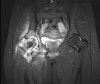

MRI : 화농성 고관절염(Pyogenic arthritis, Septic arthritis)